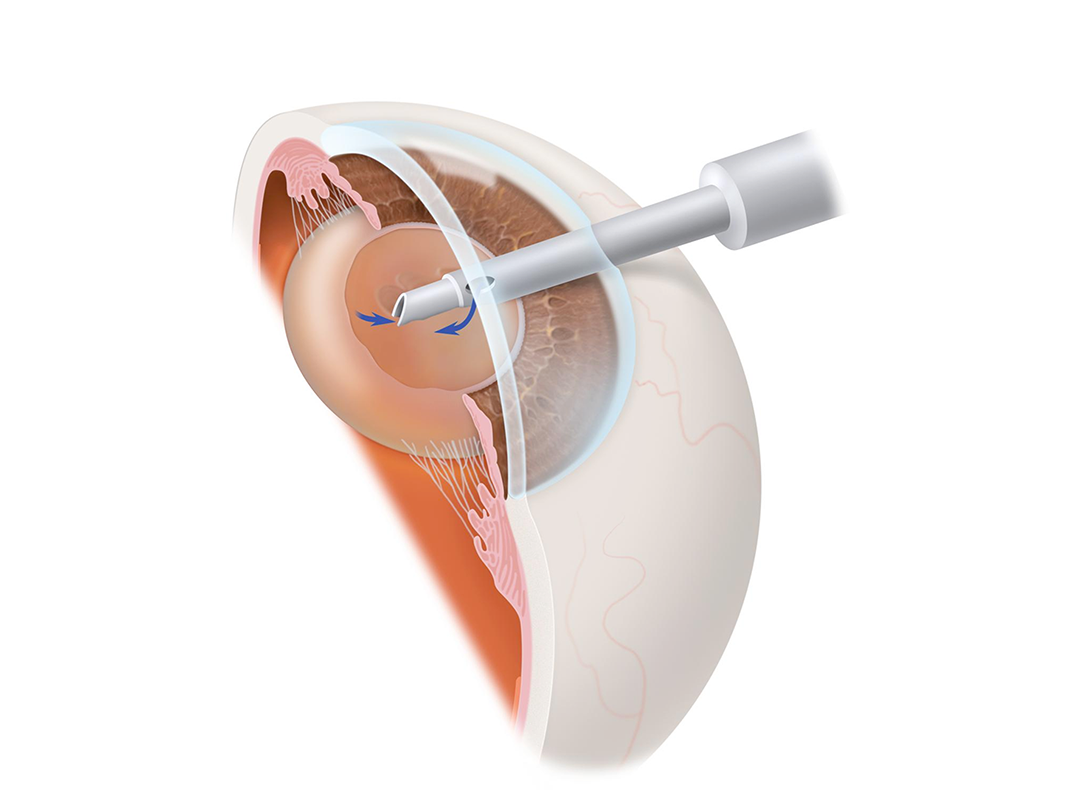

إزالة العدسة المعتمة باستخدام الموجات فوق الصوتية من فتحة صغيرة بدون غرز، مع سرعة تعافي عالية ونتائج بصرية ممتازة.